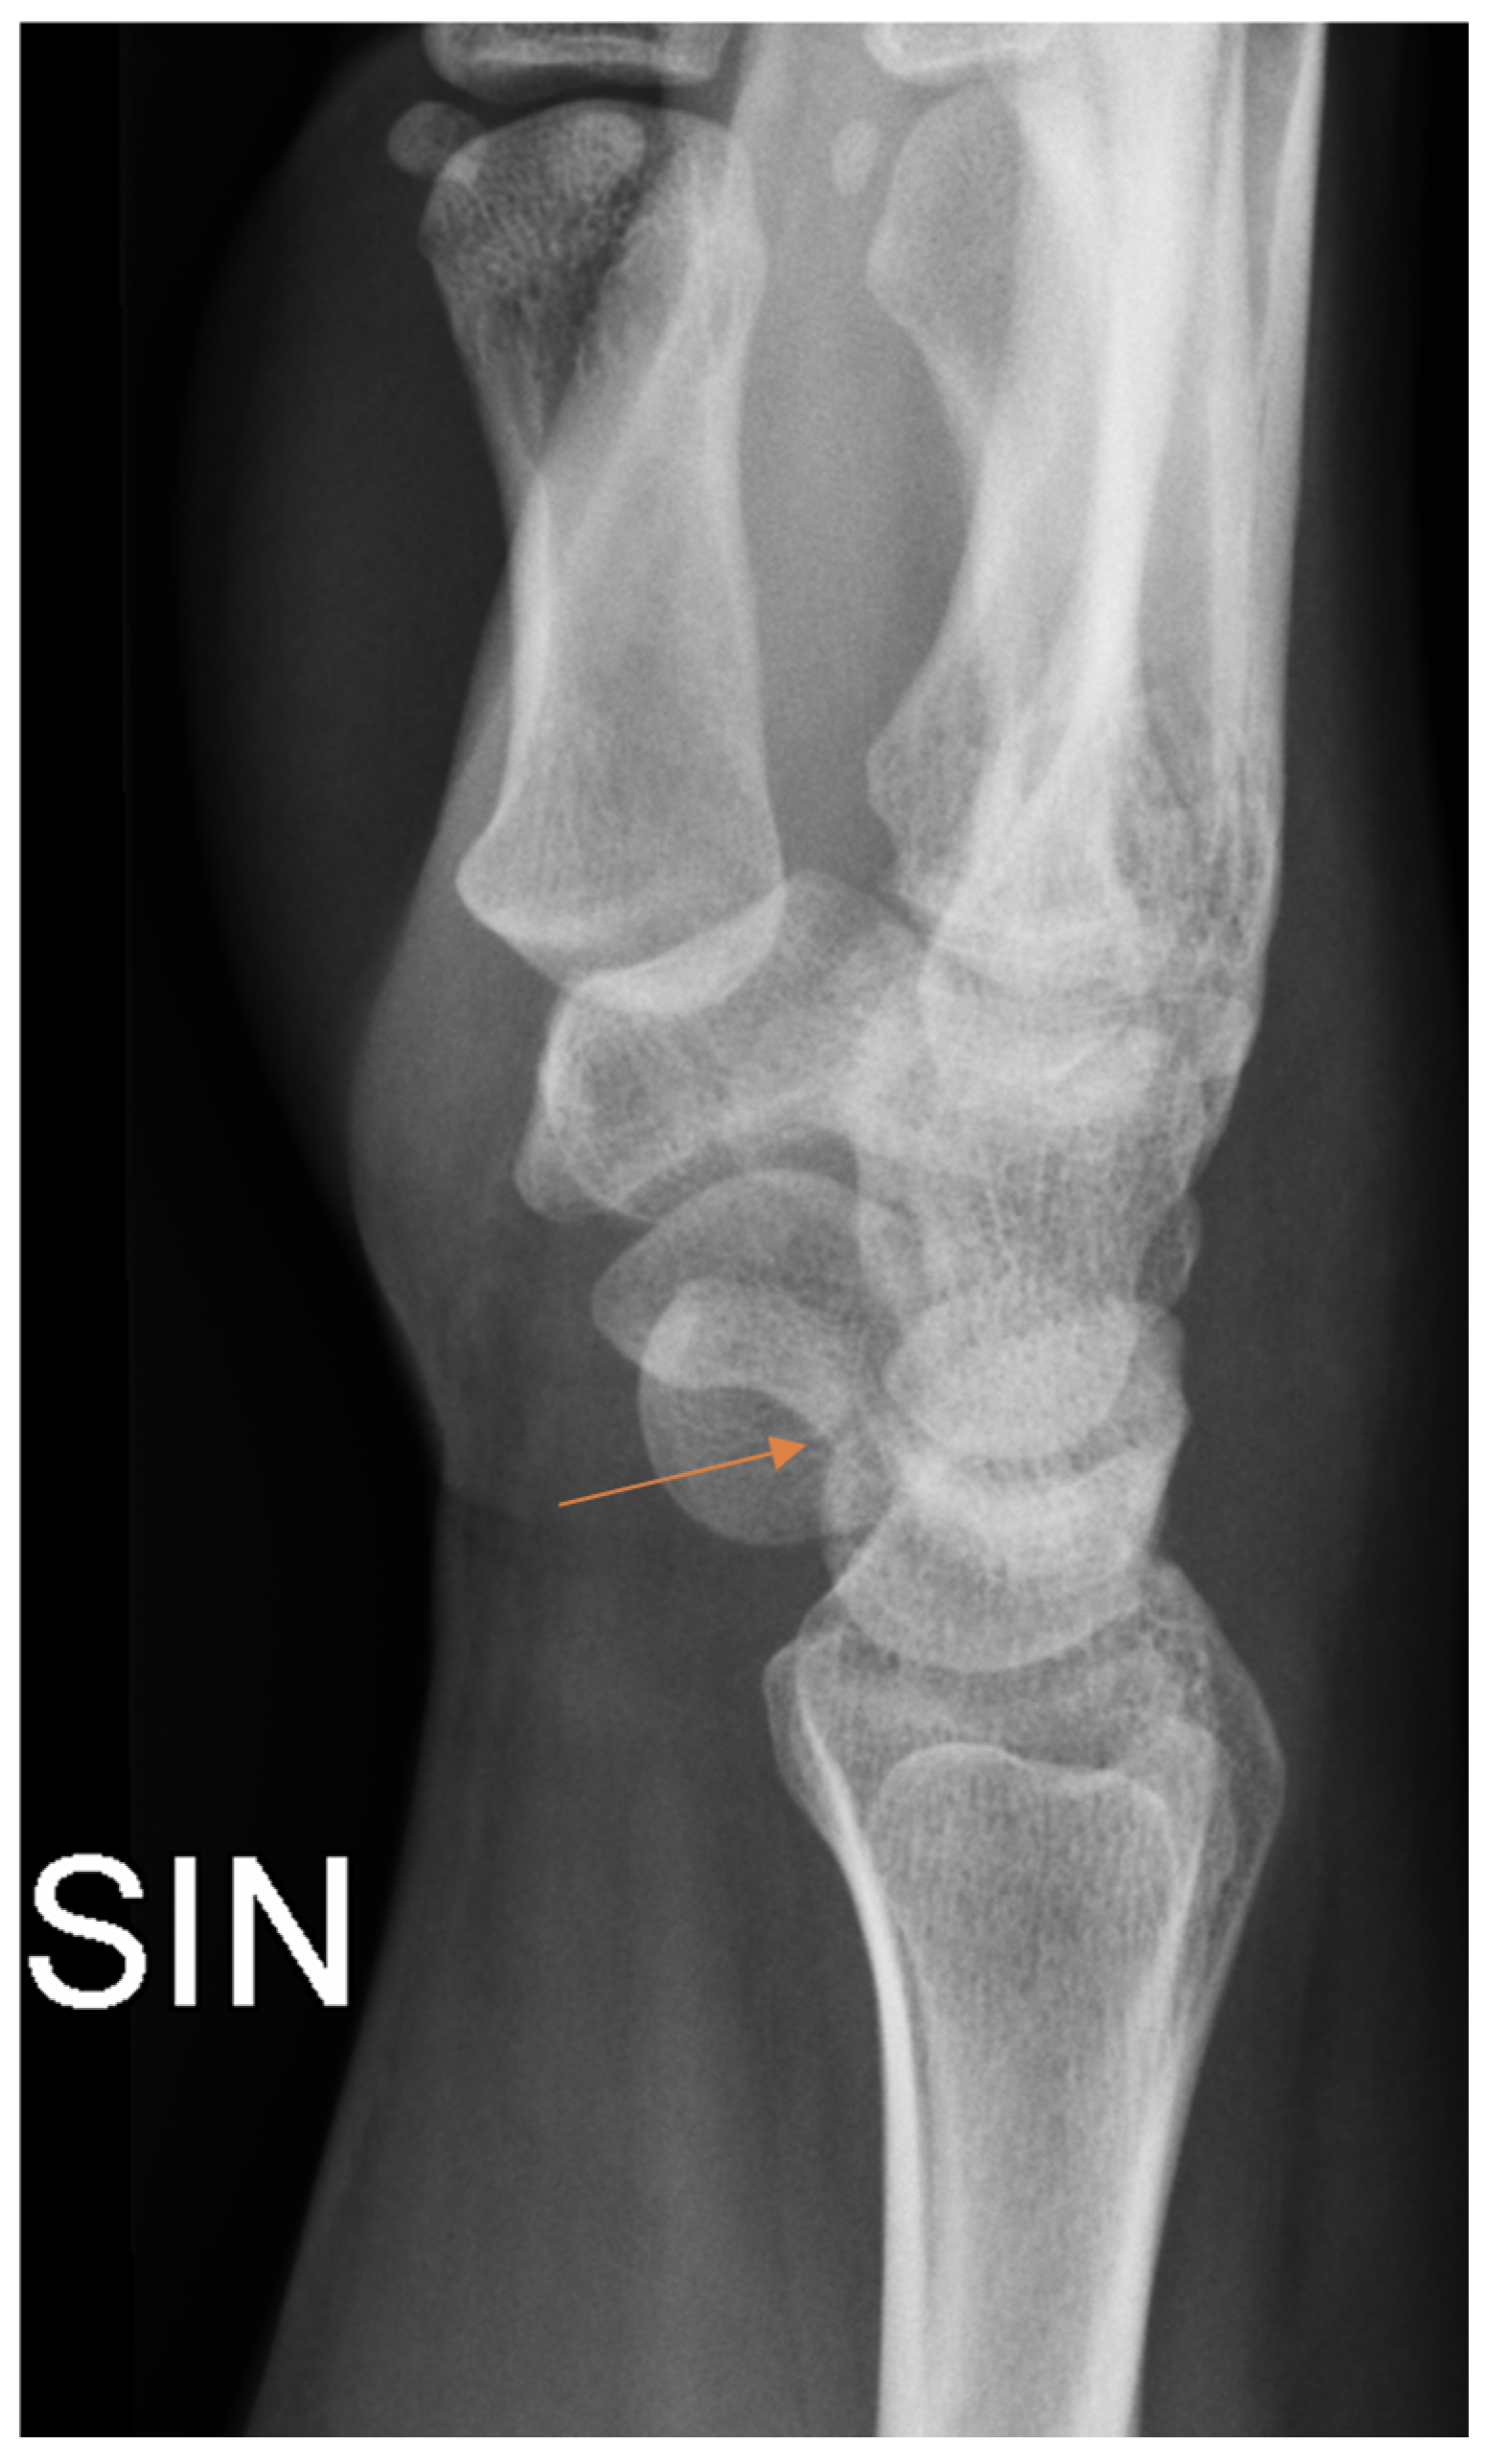

Radiology specialists interpreted more radiographs as having subtle findings compared to residents (p = 0.04). Different age groups did not differ (p = 0.89) between subtle or obvious cases. Radiology specialists missed correct diagnoses in subtle and obvious radiographs in 33% and 4.9%, respectively. In contrast, residents missed correct diagnoses in subtle (Figure 2) and obvious (Figure 3) radiographs in 51% and 8.4%, respectively.

Figure 2.

Subtle radiographic finding in patient with scaphoid fracture (arrow) that was initially missed by the resident.